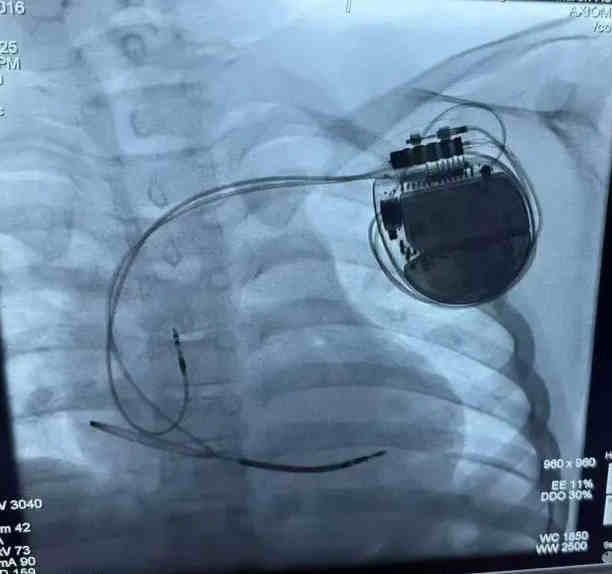

經(jīng)過(guò)充分的術(shù)前準(zhǔn)備,李磊團(tuán)隊(duì)為小宇實(shí)施了ICD植入術(shù)。手術(shù)在局部麻醉下進(jìn)行,團(tuán)隊(duì)?wèi){借精湛的技術(shù),精準(zhǔn)地將電極導(dǎo)線經(jīng)靜脈植入小宇的右心室,并將ICD脈沖發(fā)生器埋藏于左胸前皮下。整個(gè)手術(shù)過(guò)程順利,耗時(shí)約1.5小時(shí),小宇無(wú)明顯不適。術(shù)后,小宇在醫(yī)護(hù)人員的精心照料下恢復(fù)迅速,精神狀態(tài)良好,食欲也逐漸恢復(fù)。經(jīng)過(guò)一周的觀察與護(hù)理,小宇順利出院,回到了溫暖的家庭懷抱。從此,他再也不用擔(dān)心暈厥的困擾,可以像其他孩子一樣盡情玩耍、快樂(lè)成長(zhǎng)。